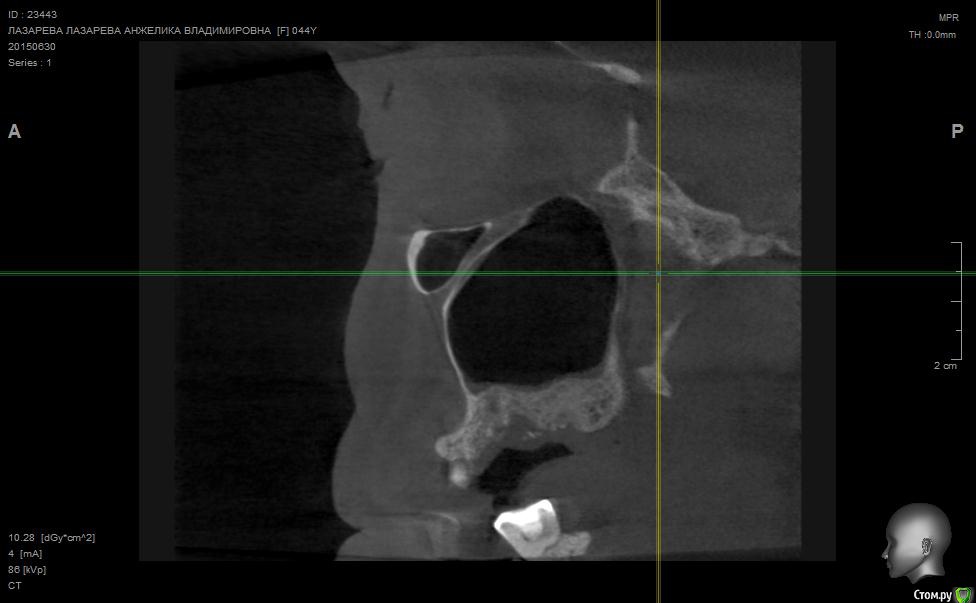

Angelika Опубликовано 2 июля, 2015 Поделиться Опубликовано 2 июля, 2015 Добрый день!Помогите,пожалуйста!!!!!!8 мая имплантолог(!) удалил 2 зуба-27(резерцин-формалиновый) и 28 (нелеченный).Удаление было очень долгим и травматичным,почуяв неладное,хотела убежать прямо из кресла.Последствия-одонтогенный гайморит,не считая незаживающих лунок .В начале июня отлежела в ЧЛХ(антибиотики,физио).26 июня сделала КТ.Нос пришел в норму более-менее,а вот челюсть....((((( Из заключения: 26,27,зубы отсутствуют. В альвеолярном отростке верхней челюсти в области отсутствующего 26 и 27 зуба визуализируется дефект костной ткани размерами до 9,6*14,0*7,2 мм с неровными и нечеткими контурами, с множественными мелкими и крупными секвестрами, с разрушеннымиоральной кортикальной пластинкой альвеолярного отростка верхней челюсти на протяжении до 12,9мм, и вестибулярной замыкательной пластинкой на протяжении до 19,1 мм. Рентгенологическихпризнаков свидетельствующих о наличии свищевого хода, ороантрального соустья - не выявлено,целостность нижней стенки левой верхнечелюстной пазухи полностью восстановлена на всем протяжении. Положительная динамика от 26.05.15г. В альвеолярном отростке, в области корней отсутствующего 28 зуба, определяются нечеткиеконтуры лунки удаленного зуба и единичный фрагмент корня размерами до 1,9*1,7*2,7 мм. В областиотсутствующего 28 зуба и бугра верхней челюсти слева визуализируются единичные мелкие участки остеопороза костной ткани альвеолярного отростка верхней челюсти, в следствие исхода воспалительного процесса. Посоветуйте,пожалуйста,нужно ли удалять обломок корня 28 зуба,если он такой маленький,а лунка уже затянулась.Что мне делать,как это залечить,болит вся челюсть с левой стороны.(((((( О имплантах и забыла уже,восстановиться бы после такой травмы.....Помогите!!! Что делать,как залечить все это?Снимки прилагаю. Ссылка на комментарий

Alejandro Опубликовано 2 июля, 2015 Поделиться Опубликовано 2 июля, 2015 На бумаге страшнее, чем на снимке. Лучший врач для Вас теперь - время. Со временем, кстати, станет понятно: что делать с остатком корня, экстренности пока никакой нет. Успокойтесь, сложные удаления довольно часто встречаются. Очень хорошо, что нет ороантрального сообщения. 2 Ссылка на комментарий

Bier Опубликовано 5 июля, 2015 Поделиться Опубликовано 5 июля, 2015 нет. У Вас на рентгене картина свежего удаления. Т.е. в рамках нормы 2 Ссылка на комментарий

Bier Опубликовано 7 июля, 2015 Поделиться Опубликовано 7 июля, 2015 думаю, что проблем там нет. На снимке все не так плохо, как в описании. Все хорошо будет. Ссылка на комментарий